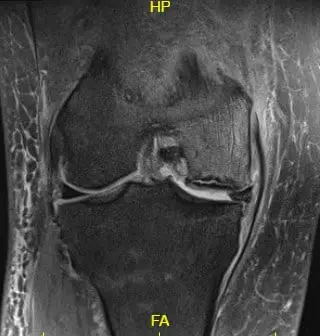

Imaging studies revealed severe osteoarthritis of the medial compartment of the right knee along with patellofemoral arthritis. MRI revealed progression of previous subchondral fracture at the medial femoral condyle now resulting in a region of avascular necrosis and prominent fluid-filled subchondral fracture line measuring up to 2.8 cm. There was a mild collapse of the articular margin and severe surrounding bone marrow edema.

T2 weighted image showing the coronal section of the knee with altered bone marrow signal and rim sign

T2 weighted image showing the coronal section of the knee with altered bone marrow signal and rim sign.